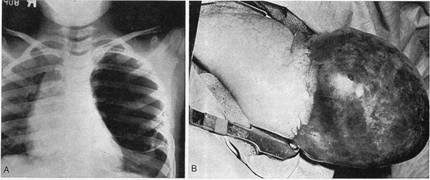

Клінічно декомпенсована, або гостра локалізована, вроджена емфізема проявляється у новонароджених у перші дні життя. Для неї характерні класичні прояви синдрому внутрішньолегеневого напруження: гостра, прогресуюча дихальна недостатність, наростаюча задишка, напади кашлю та ціанозу, тахікардія. Діти неспокійні, положення тіла вимушене на хворому боці, під час дихання візначається втягнення міжреберних проміжків, випинання ураженої половини грудної клітки, її відставання в акті дихання. Органи межистіння різко зміщені в здоровий бік, перкуторно — на ураженому боці тимпаніт, аускультативно - дихання відсутнє. На рентгенограмі (Мал.14.)

Мал.14. Вроджена лобарна емфізема верхньої долі лівої легені.

визначають посилену прозорість легеневого малюнку майже до його відсутності на боці ураження, виявляють затемнення трикутної форми, які прилягають до межистіння і зумовлені ділянками відтиснутої, колабованої легеневої паренхіми. Купол діафрагми сплощений. Уражена частка легені пролабує в здоровий бік з утворенням межистинальної грижі.